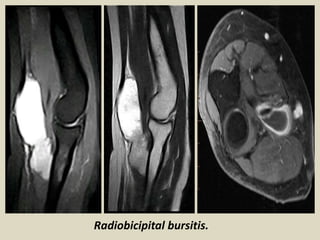

Radiobicipital bursitis.

Bicipitoradial bursitis: axial T1, T2-weighted image showing a isointense

enlarged bicipitoradial bursa. Green arrow: biceps tendon.